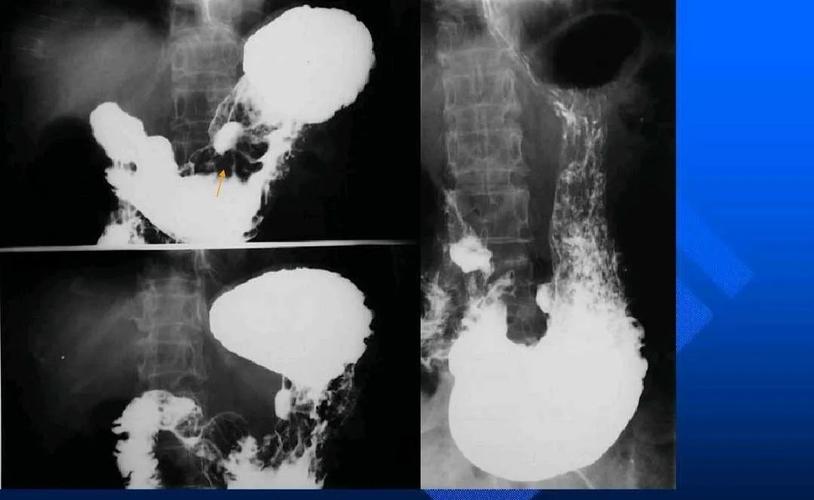

上消化道造影检查技术及常见病变的x线诊断

上消化道造影图片讲解

消化道造影